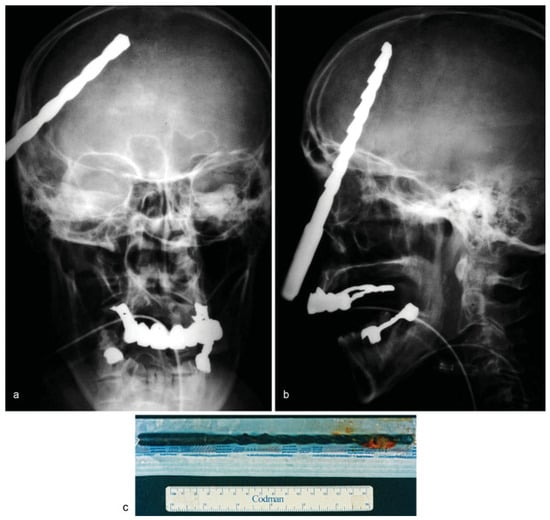

• Case 6: A 53-year-old patient suffered an impalement injury with a metallic drill, which had penetrated his neurocranium. The patient had tried to commit suicide, injuring himself in the thorax and head (Figure 6a,b). MDCT imaging displayed the position of the impacted drill, which had entered the skull at the front temporal cortex, and there was also an injury of the lung parenchyma (not shown). Following immediate thoracotomy to stabilize the patient, the drilling device was completely removed by osteoclastic trepanation performed by our colleagues in the neurosurgery department (Figure 6c). However, the patient subsequently died due to increased cerebral edema and severe damage to the brain parenchyma.

Figure 6. (a,b) Frontal and lateral skull radiographs showing a radiopaque foreign body penetrating intracranially. (c) Postoperative image of the metallic drill.